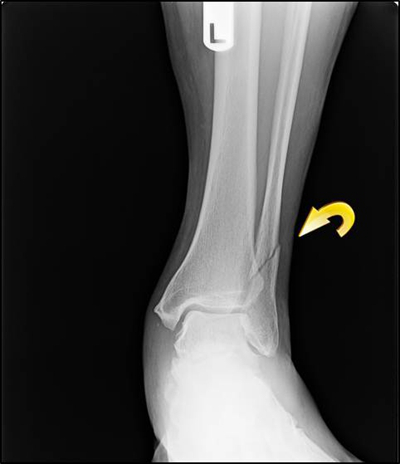

骨折圖片